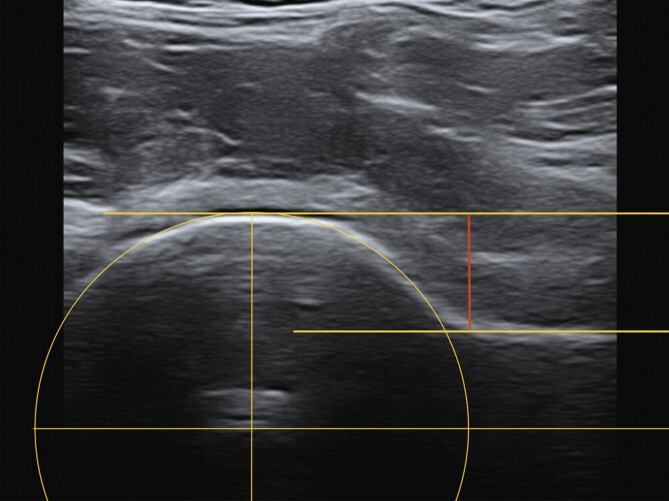

目的:x线,磁共振成像(MRI)和计算机断层扫描(CT)是确定股骨-髋臼撞击(FAI)头颈偏移(HNO)的标准方法。我们的假设是超声辅助确定髋关节CAM畸形的偏移量是一种便宜、无辐射、可靠的替代传统的α角测定方法。方法:在2015年1月至2019年12月期间,根据DEGUM标准程序和MRI进行前纵行髋关节超声检查的髋关节疼痛和疑似CAM撞击患者纳入本单中心研究。偏移量由两名独立调查员通过MRI和超声检查确定三次。结果:285例患者中,110例患者(女性49例,男性61例)符合纳入标准。54例左髋关节和56例右髋关节调查时的平均年龄为54.2岁。进行了1320次测量。MRI (6.11 mm+/-2.37)与超声(5.93 mm+/-2.20)检测HNO无显著差异。平均差值为0.32 mm±0.32 mm (p < 0.05),最大偏差为2.08 mm(异常值)。结论:超声辅助测定头颈偏移是一种可靠、可重复性高的方法,其准确性不低于MRI。超声检查最初可作为定性确定髋关节CAM畸形的替代或附加工具。

Purpose: Native X-ray, magnetic resonance imaging (MRI), and computed tomography (CT) are standard methods for determining head-neck offset (HNO) in femoro-acetabular impingement (FAI). Our hypothesis was that sonography-assisted determination of the offset in CAM deformity of the hip is a cheap, radiation-free, and reliable alternative to conventional alpha-angle determination.

Methods: Patients with hip pain and suspected CAM impingement who underwent anterior-longitudinal hip sonography according to DEGUM standard procedures and MRI were included in this single-center study between January 2015 and December 2019. Offset was determined three times on MRI and sonography by two independent investigators.

Results: 285 patients were screened and 110 patients (49 females, 61 males) met the inclusion criteria. The mean age at the time of investigation of 54 left and 56 right hip joints was 54.2 years. 1320 measurements were performed. No significant difference in HNO determination between MRI (6.11 mm+/-2.37) and sonography (5.93 mm+/-2.20) could be identified. The mean difference was 0.32 mm+/-0.32 mm (p>0.05) with a maximum deviation of 2.08 mm (outlier).

Conclusion: Sonography-assisted determination of head-neck offset is a reliable and reproducible method and is not inferior to determination with MRI. Sonography can be used initially as an alternative or additional tool for the qualitative determination of CAM deformity of the hip joint.